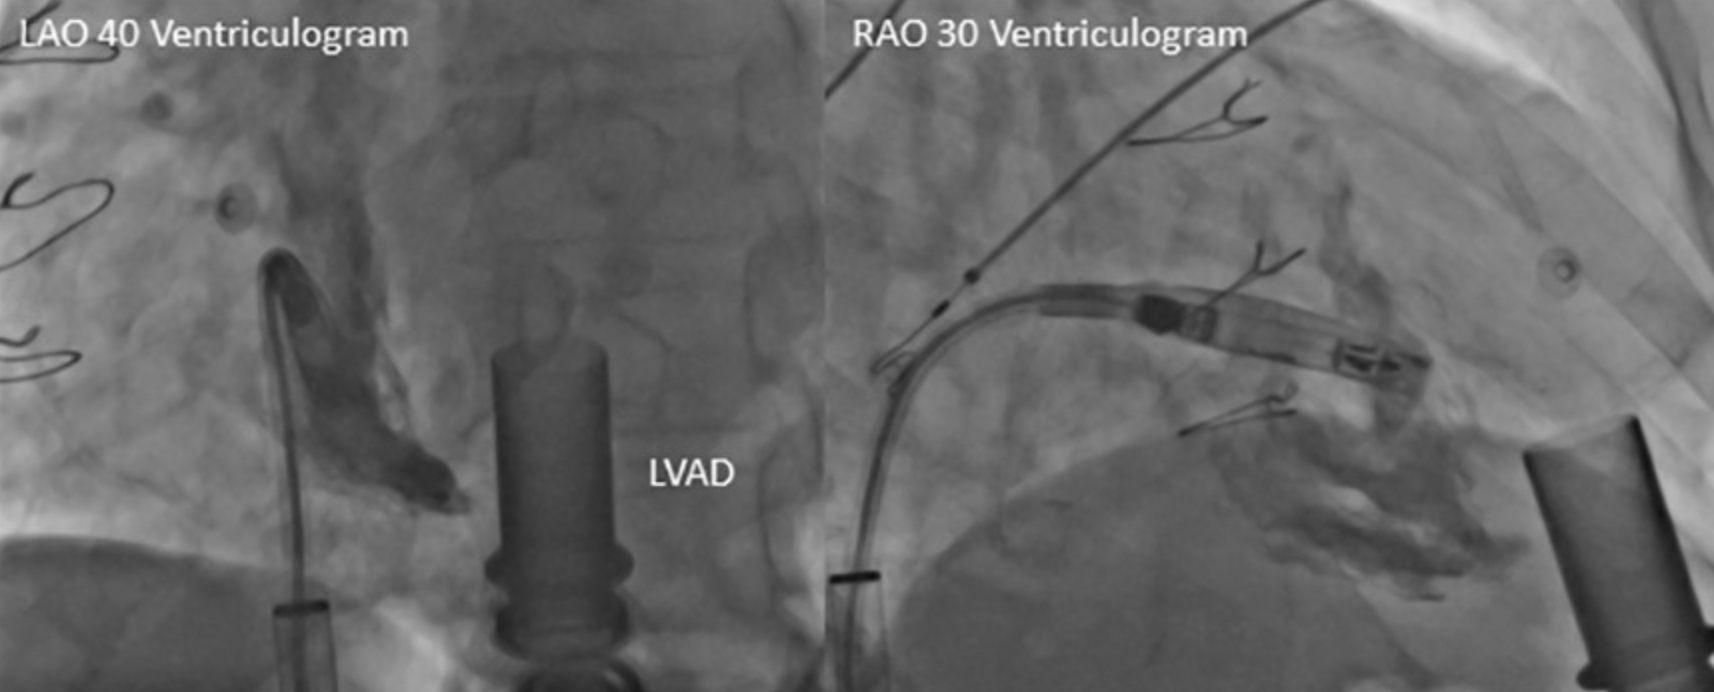

• 在术中,术者按照标准植入流程植入了心室无导线起搏器:导管跨过三尖瓣后,通过造影明确了低位间隔的最佳植入位置,随后通过Mapping标测确定了最佳旋入点,后进行旋入固定;心房无导线起搏器同样按标准植入流程植入于右心耳基底部(图1、2、3)。

图1 心室无导线起搏器植入时RAO和LAO造影